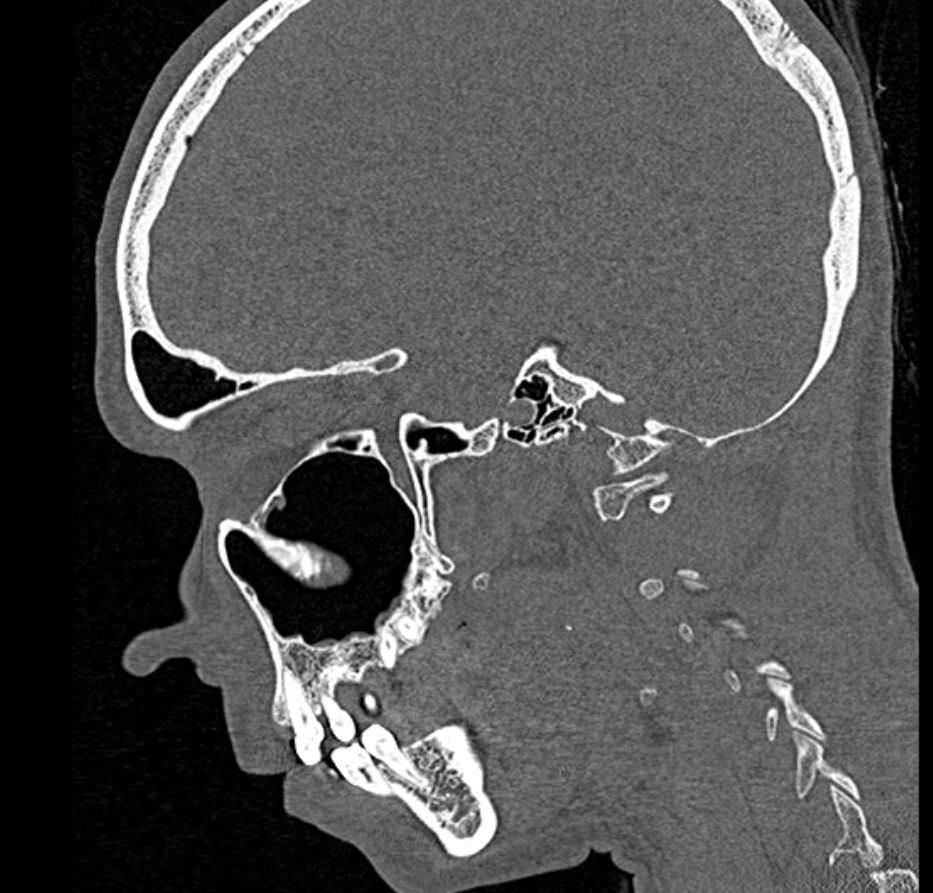

Мультиспиральная компьютерная томография относится к высокоинформативным лучевым методам исследования, то есть основана на применении рентгеновского излучения и различной способности тканей поглощать рентгеновские лучи. Костные структуры обладают наибольшей плотностью по сравнению с другими тканями, поэтому в большей степени поглощают рентгеновские лучи и лучше всего визуализируются при данном исследовании. Благодаря этому КТ позволяет детально изучить кости лицевого черепа, а также углубления, которые являются вместилищем для важных органов (глазницы, полость носа, ротовая полость).

КТ мягких тканей лица является наиболее информативным методом диагностики травматических повреждений лица, посттравматических деформаций, аномалий развития, инородных предметов в носовой полости и околоносовых пазухах. Кроме того, мультиспиральная КТ применяется для выявления скрытых воспалительных процессов, нарушений кровообращения в области лица, а также используется при планировании оперативного вмешательства (в том числе, пластических операций) и в дальнейшем применяется в послеоперационном периоде для оценки успешности проведенной операции.

Детальные изображения костей лицевого черепа и мягких тканей лица получаются за счет вращения трубки томографа с излучателями рентгеновских лучей вокруг объекта исследования. В аппаратах увеличено количество сверхчувствительных детекторов, позволяющих производить множество послойных снимков с толщиной среза от 0,5 мм, которые затем преобразуются в трехмерные пространственные модели лицевого черепа с окружающими тканями. Такие инновационные возможности аппаратов обеспечивают проведение точной и достоверной диагностики.